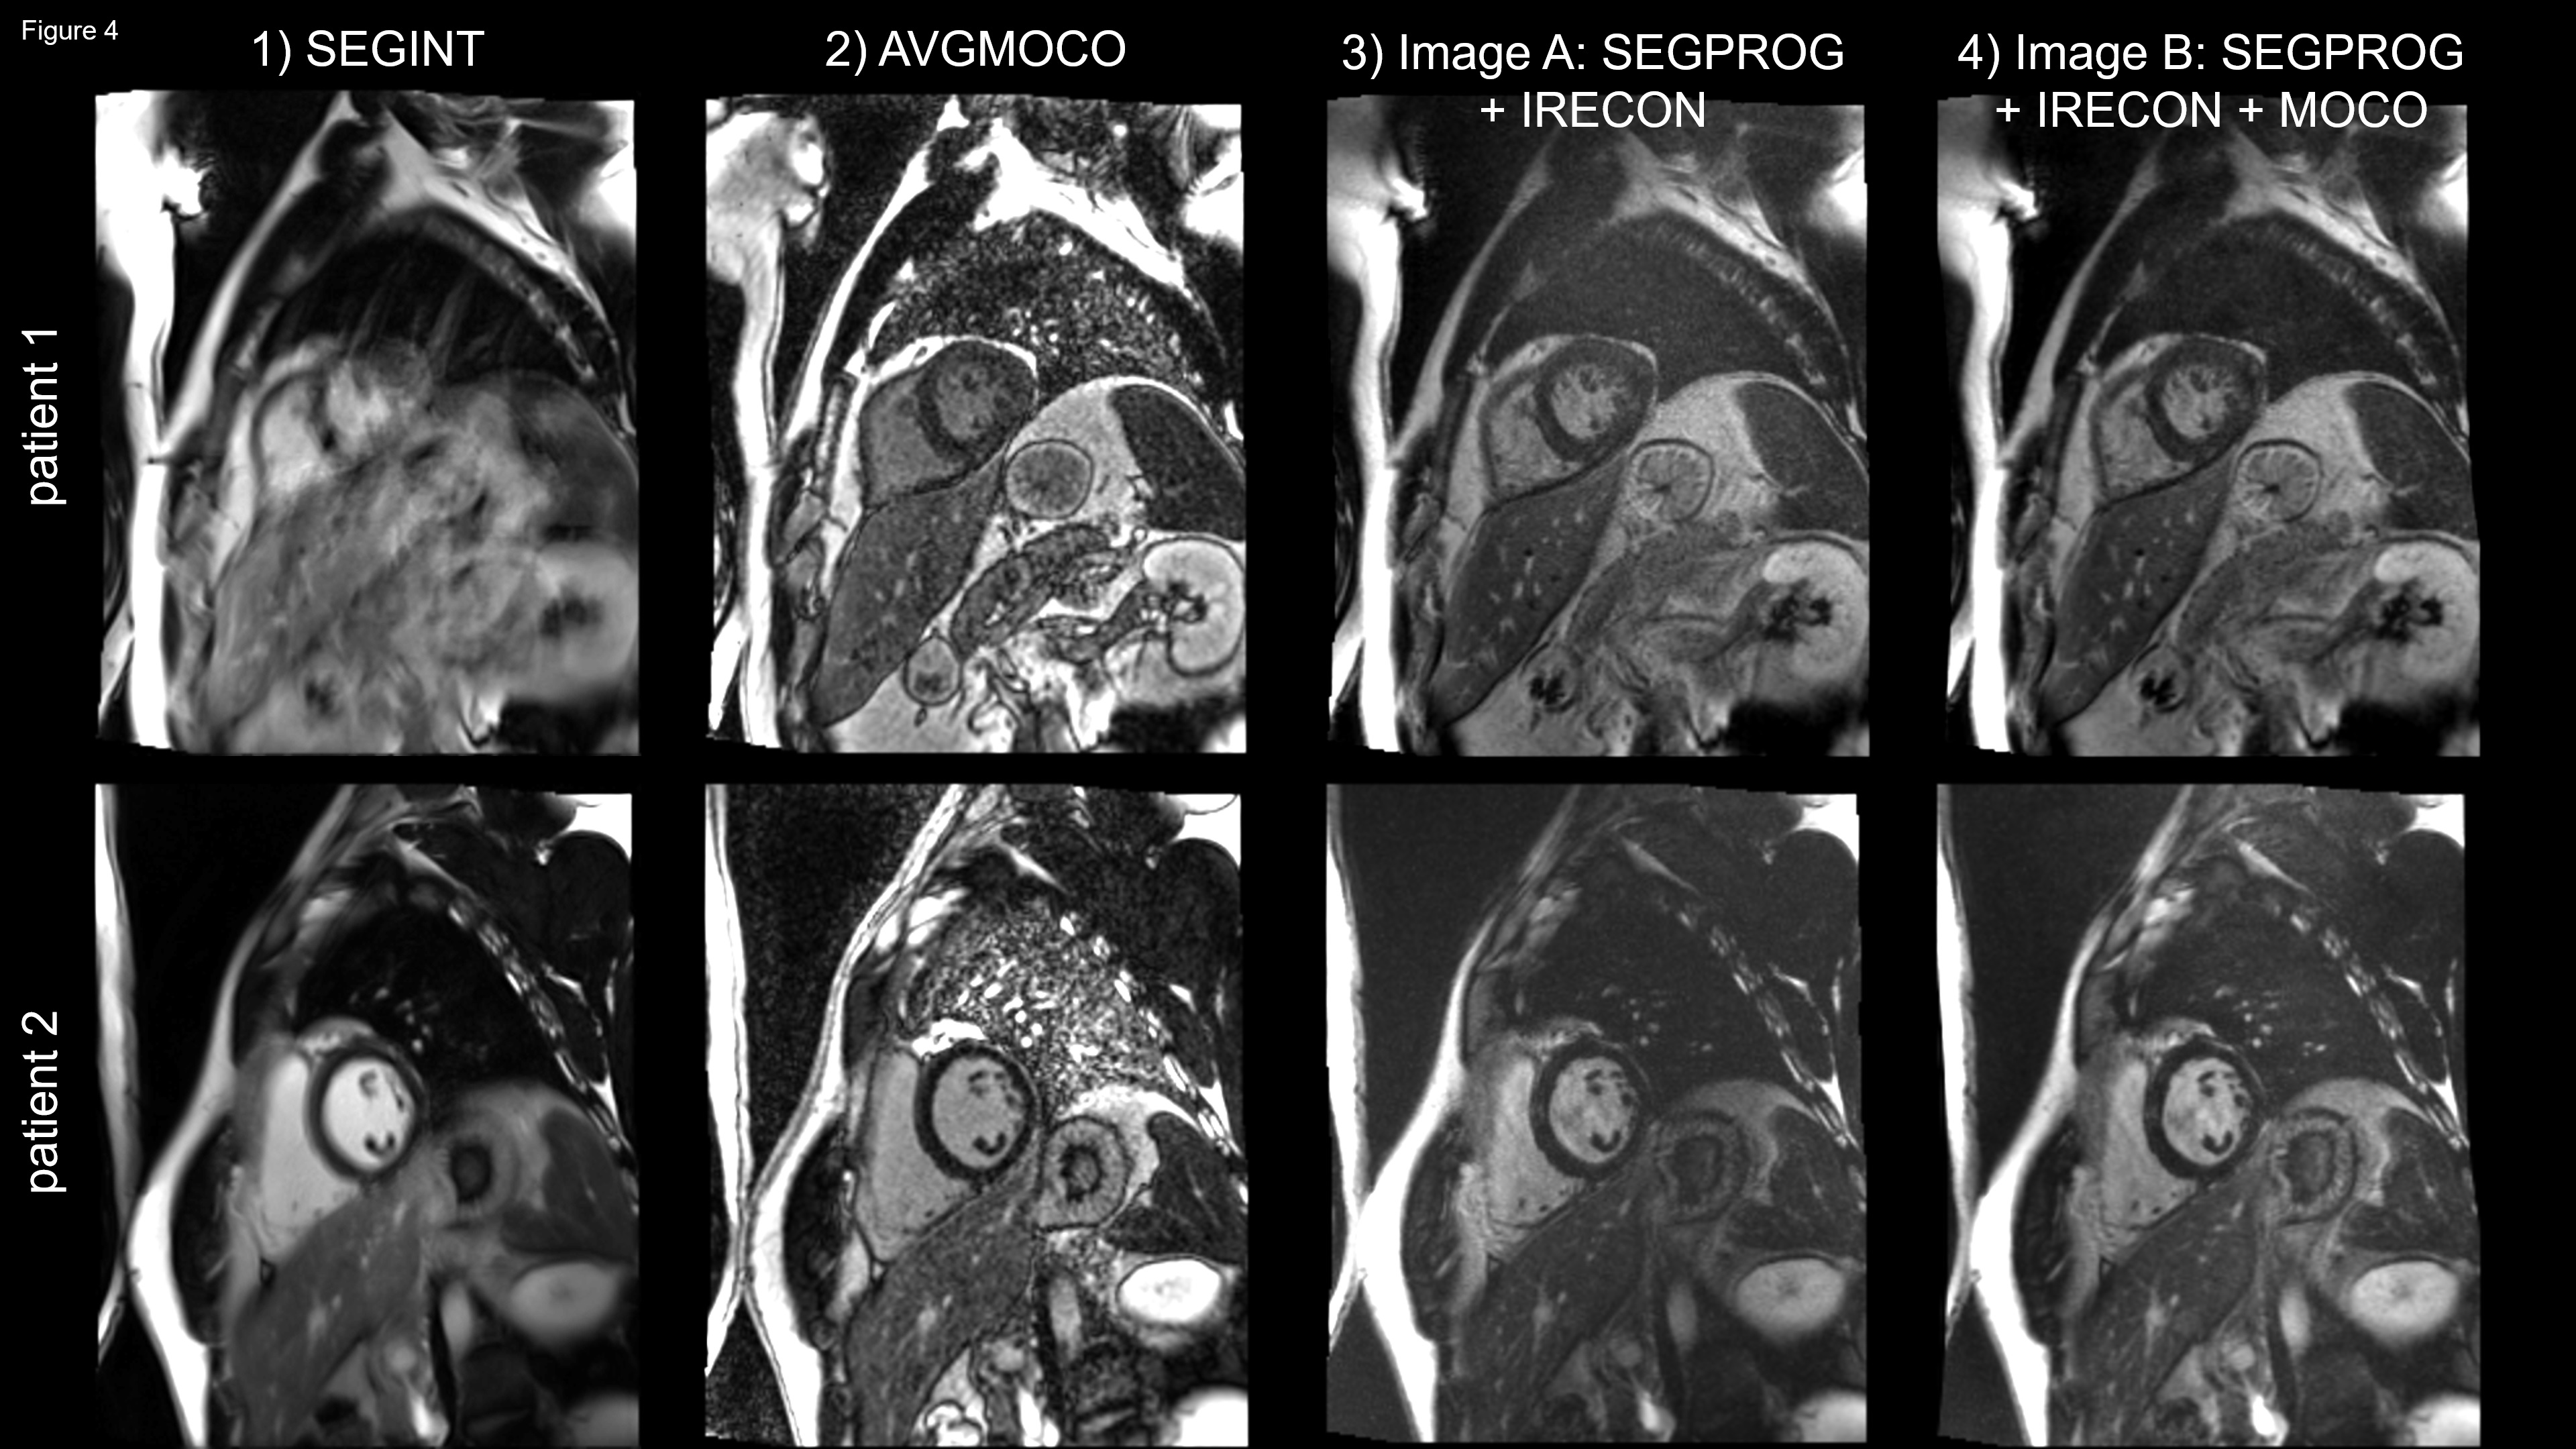

In patient 1 (Figure 4), the SEGINT image is blurred and nondiagnostic. Severe ghosting results from the sensitivity of INT reordering to motion. The AVGMOCO image has no ghosting artifacts but low SNR. SEGPROG image A using IRECON looks like a BH image, has higher SNR than the AVGMOCO, no ghosting artifacts, and good myocardium to blood contrast. The segment based MOCO slightly improves papillary muscle sharpness (image B). The images of patient 2 tell a similar story.

Upper row: mid-ventricular short-axis slice of a cardiac patient. 1) The SEGINT image is nondiagnostic. Breathing causes blurring and ghosting of the chest wall. 2) The AVGMOCO image has no artifacts but low SNR, due to matching spatial and temporal resolution and used shots per image to SEGPROG. 3) SEGPROG is FB but looks like a BH image, has higher IQ and SNR than AVGMOCO, no ghosting, and good myocardium to blood contrast. 4) The segment based MOCO slightly increases the sharpness of the papillary muscles.

Lower row: example similar to the above except that the SNR is higher, for all images.